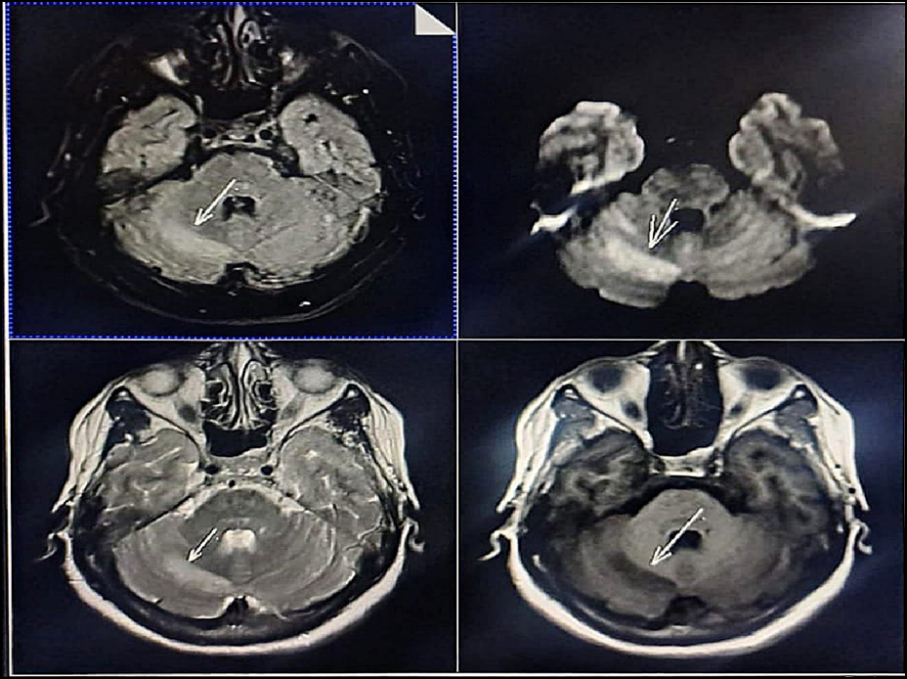

A 53-year-old-female presented to the emergency medical ward with chief complaints of sudden fall and was found unconscious in the bathroom around 2 PM with a gas geyser in use. On admission the patient exhibited altered sensorium, accompanied by irritability and restlessness with no prior medical history. Systemic examination was normal overall, with dyspnea noted on respiratory examination, sedation/drowsy and unsteadiness on neurological assessment and weakness on musculoskeletal evaluation. The Glasgow Coma Score (GCS) was E2V3M5, vitals were stable and the patient was afebrile. Random blood glucose (GRBS) was elevated at 338 mg/dL following which HbA1C, CBC and MRI investigations were ordered. The HbA1C level was 5.6 %, CBC was normal with increase in WBC count (14030 mcL), and MRI findings revealed subacute infarcts involving bilateral, medial, temporal lobes and in the right cerebellar hemisphere as shown in figure no 01. On the day following admission, the patient was conscious as well as oriented (E4V5M6) and a carotid doppler examination was conducted which demonstrated normal color uptake, flow velocities and spectral waveforms in both carotid and vertebral arteries, with no evidence of hemodynamically significant stenosis. On admission day, Arterial Blood Gas (ABG) report shows mixed acid-base disorder characterized by primary metabolic-acidosis with superimposed respiratory alkalosis, associated with severe hyponatremia, hyperkalemia, severe ionized hypocalcemia, and borderline lactic acidosis, with preserved oxygenation. After one day of inpatient care the ABG report shows mild metabolic acidosis with partial respiratory compensation. Based on the above subjective and objective evidence the patient was diagnosed with hypoxic ischemic encephalopathy secondary to gas geyser syndrome. Management include treatment with Inj. Pantoprazole 40mg for 8 days (OD), Inj. Ondansetron 4mg for 2 days (TID), Inj. Ceftriaxone 1gm for 8 days (BD), Inj. Piracetam 100mg for 8 days (BD) and Inj. Levetiracetam 1gm STAT f/b 500mg for 8 days (BD).

Figure 01: MRI scan with subacute infarcts and features of small-vessel ischemic change

Gas Geyser Syndrome is a less widely recognized but preventable form of acute hypoxic-ischemic encephalopathy caused by carbon monoxide exposure by incomplete combustion of liquified petroleum gas in home water gesyers installed in poorly ventilated bathrooms. [4] Several case reports and small case series have described unexpected collapse, altered sensorium, seizures, and long-term neurological sequelae happening in enclosed restroom environments, frequently in patients without preexisting comorbidities. [5] Inadequate ventilation causes complete burning of LPG, resulting in the accumulation of CO poisoning that leads to headache, dizziness, and confusion. [6] Coma or seizures can occur in people with extended exposure. [7] In our patient, the rapid collapse and altered sensorium, in the absence of substantial comorbidities, together with MRI evidence of focal infarctions in metabolically susceptible regions, suggest hypoxic-ischemic damage following CO exposure. CO-induced hypoxia results from carbon monoxide binding to hemoglobin, impairing oxygen delivery, particularly affecting the brain’s high metabolic demand. Key vulnerable regions include the basal ganglia (especially the globus pallidus), cerebral cortex and white matter, hippocampus, and cerebellum, all of which are associated with cognitive dysfunction and neuropsychiatric sequelae following CO exposure. [8] CO impairs myocardial oxygen use, resulting in ischemia, arrhythmias, and cardiac failure. Reduced cardiac output exacerbates systemic hypoxia and raises mortality. Apart from the brain and heart, other organs with a high oxygen demand are impacted. The kidneys and liver may experience hypoxia. Skeletal muscle and other metabolically active tissues can also suffer secondary hypoxia injury. [9-10] The improvement in consciousness within 24 hours, as well as the normal findings on carotid doppler investigations, lend support to a toxic hypoxic rather than vascular occlusive etiology. Early detection and supportive management, such as oxygen therapy and monitoring, are essential, as it can result in irreversible neurological damage or severe consequences. In contrast to the exclusively acute infarcts found in this patient, chronic small-vessel ischemic alterations (white matter hyperintensities) are typically linked to long-term microangiopathic processes rather than acute toxic damage. These alterations are mainly found on T2/FLAIR sequences in older persons, and they are classified as age-related or vascular risk-related small-vessel disease, as opposed to focal gray matter injury caused by acute hypoxia. [11]